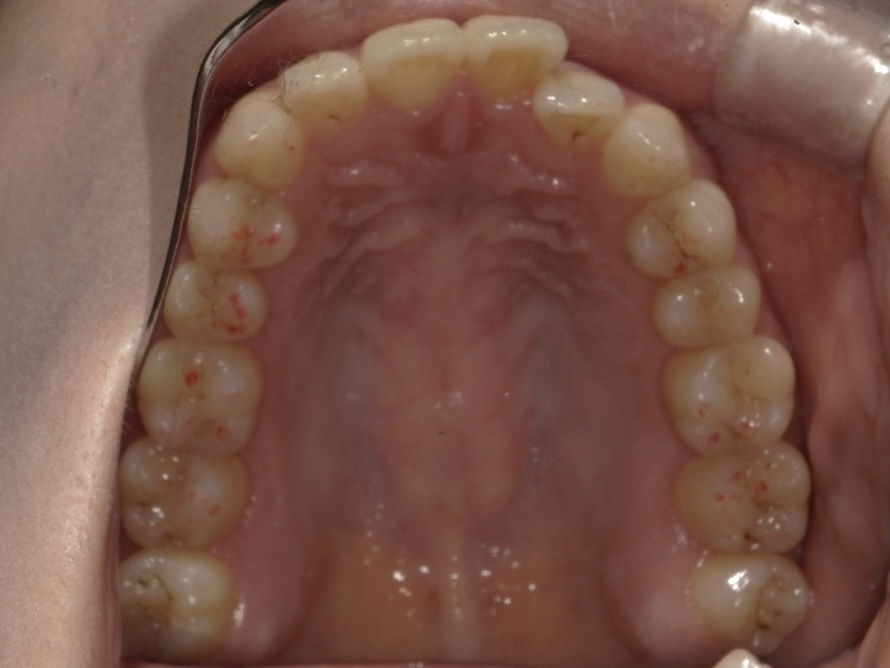

BEFORE

AFTER

| 施術内容 | 歯全体のマウスピース矯正システム「インビザラインフル」を用いた治療 |

| 治療期間 | 2年 |

| 費用 | 924,000円(税込) |